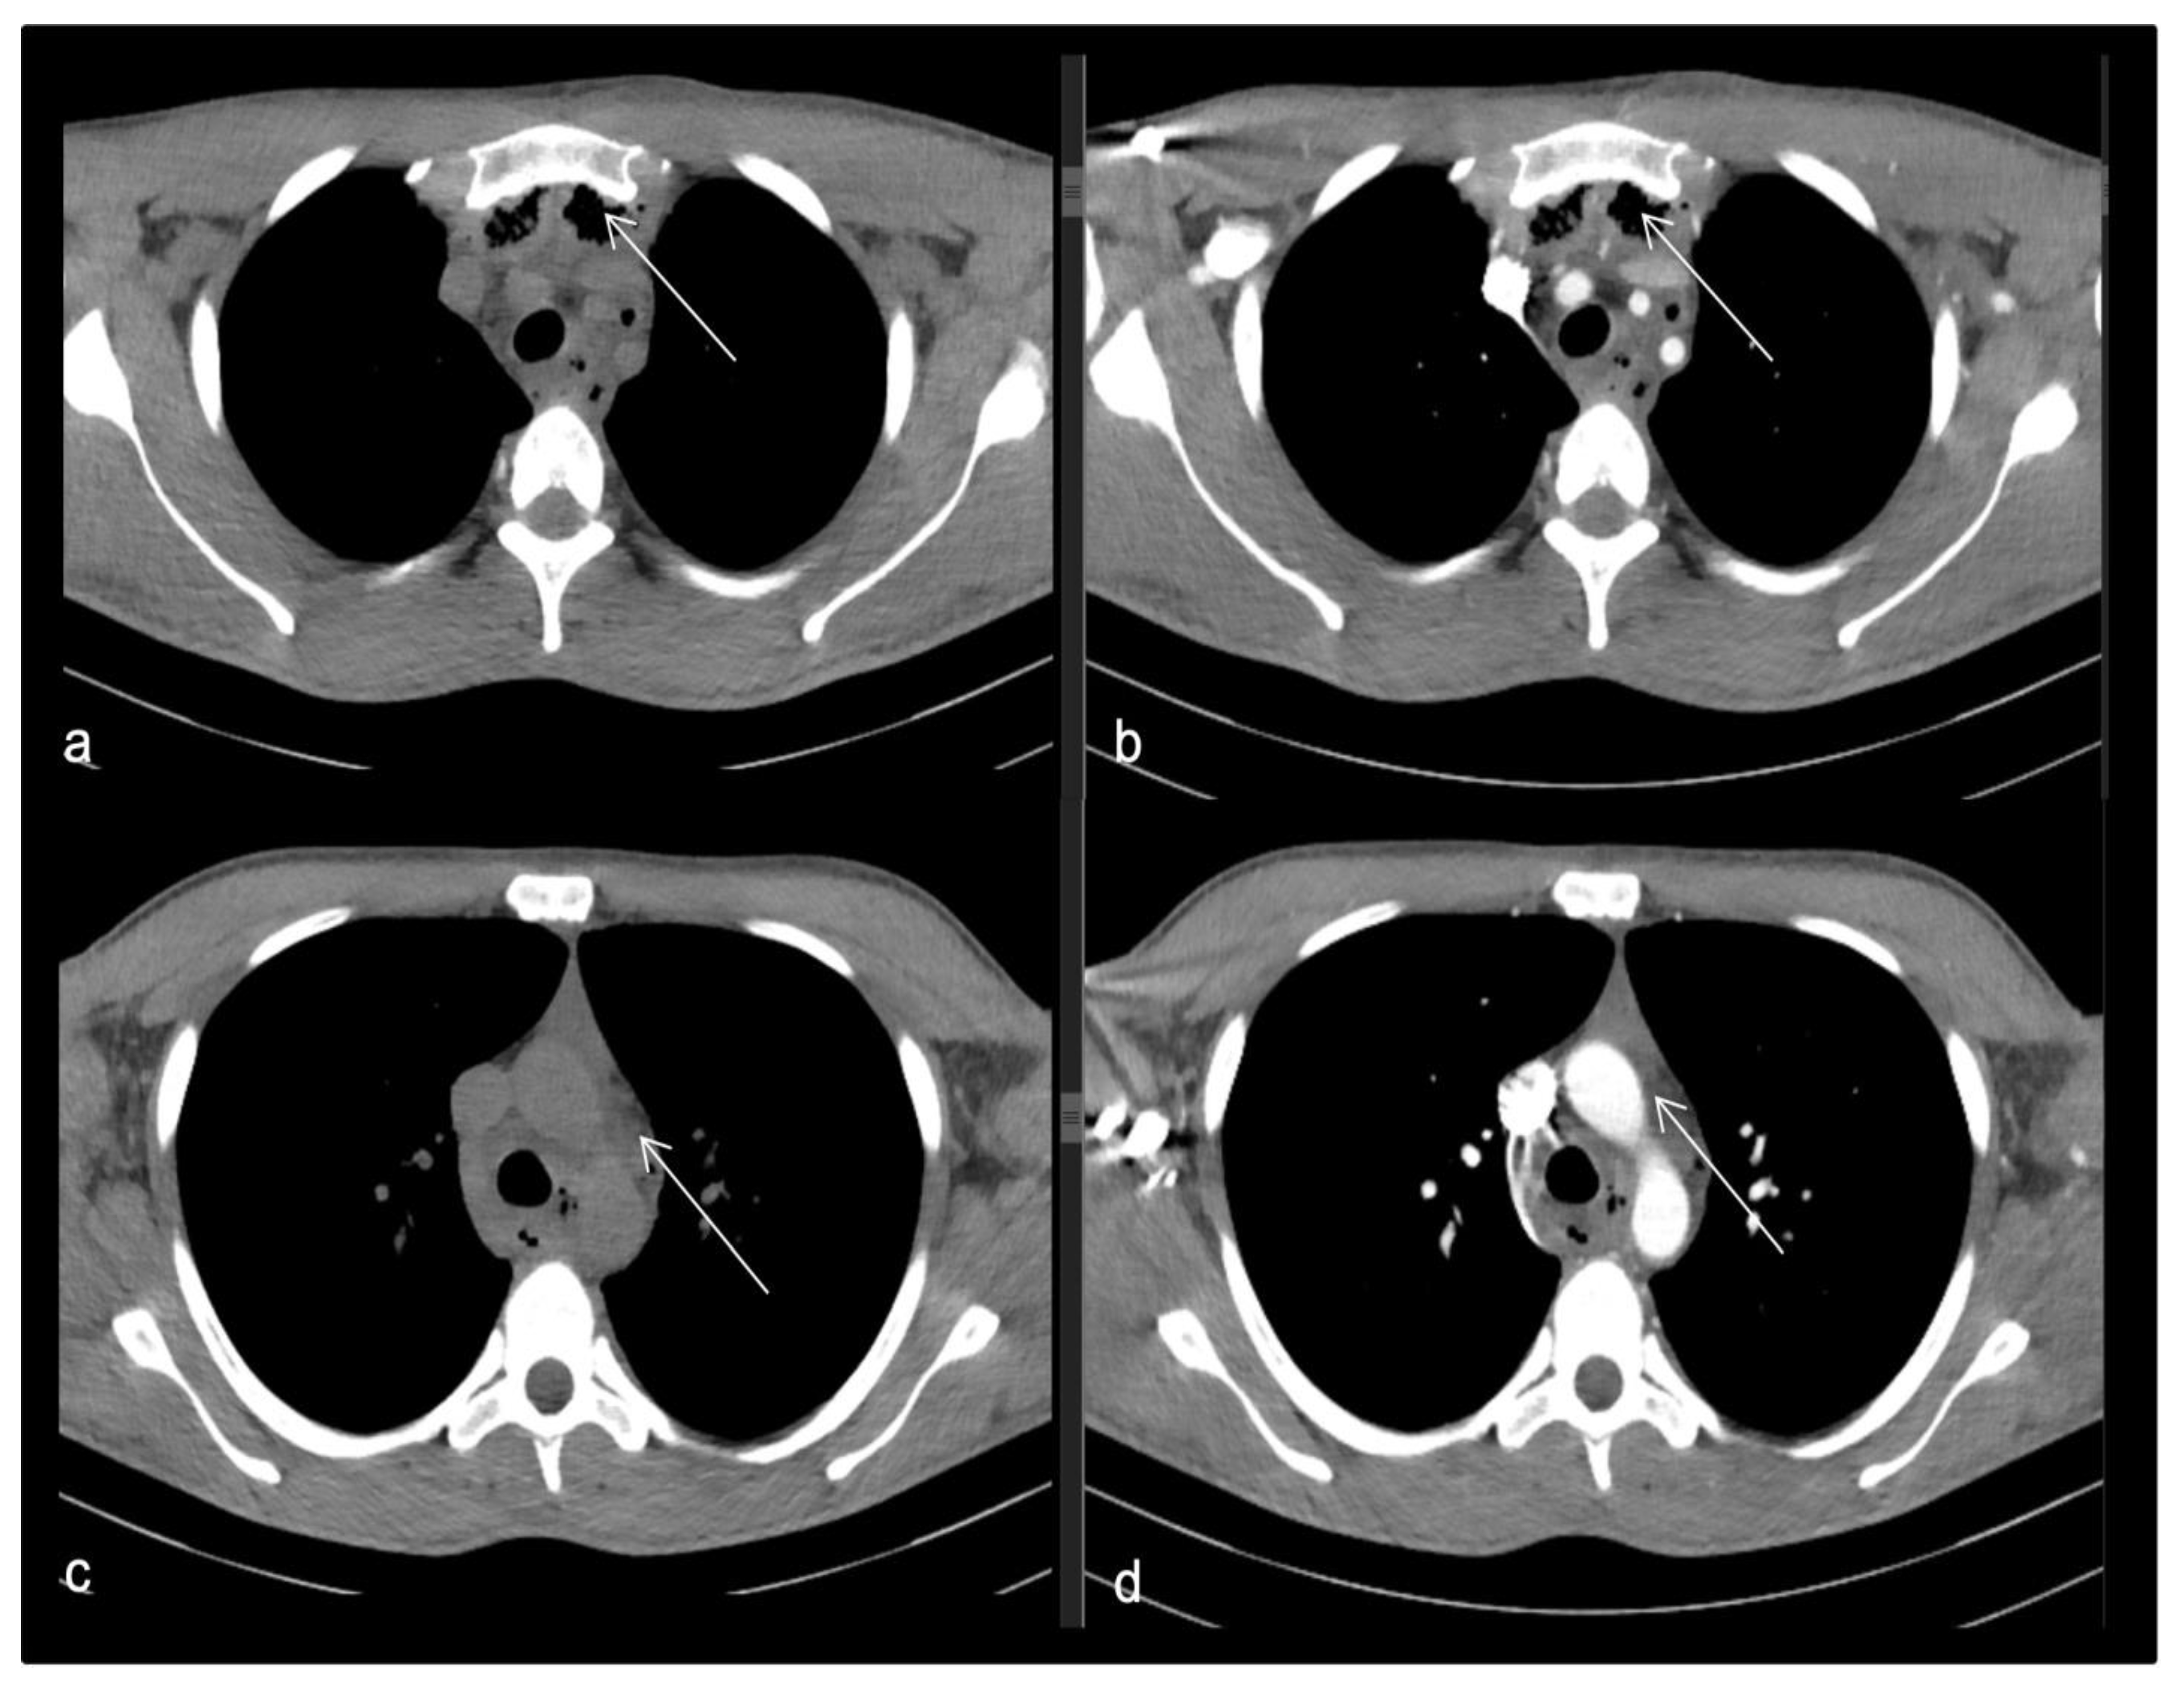

- Case 1.

- Case 2.

- Case 3.

- Case 4.